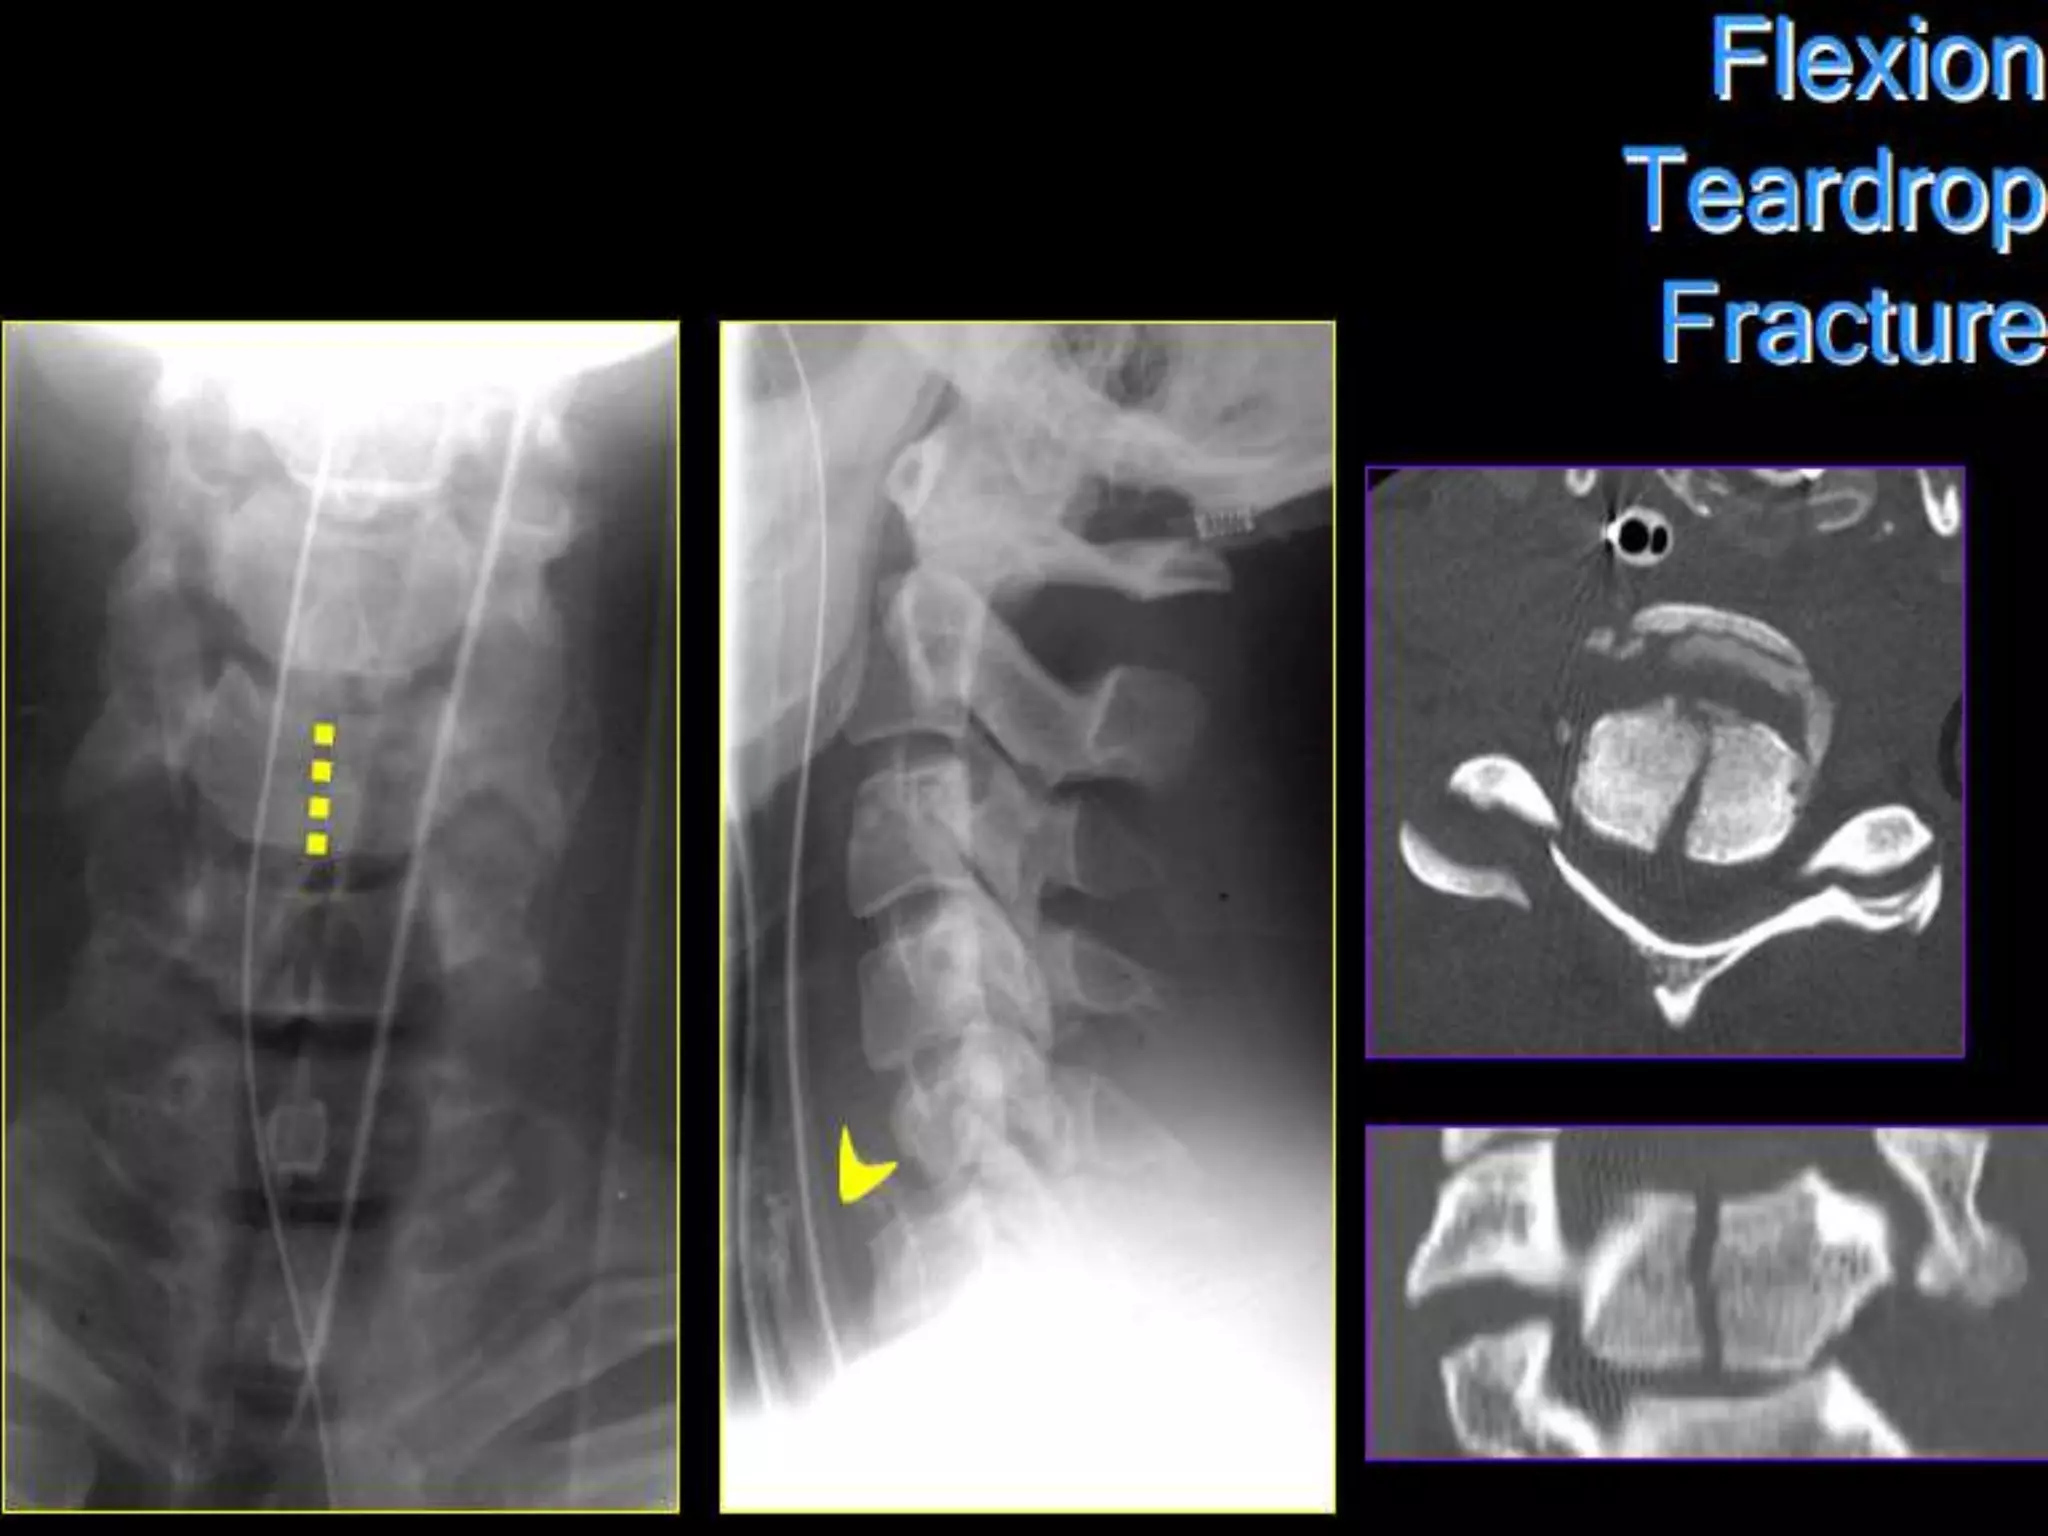

Flexion Teardrop Fracture

• Most devastating c-spine injury

compatible with life.

• Severe flexion with disruption of all

ligaments and disc + VB FX.

• UNSTABLE

Acute anterior cord syndrome

1. Complete paralysis.

2. Hypoesthesia and hypalgesia to level injury

3. Preservation touch, motion, position and

vibration sense.

Teardrop Fracture.